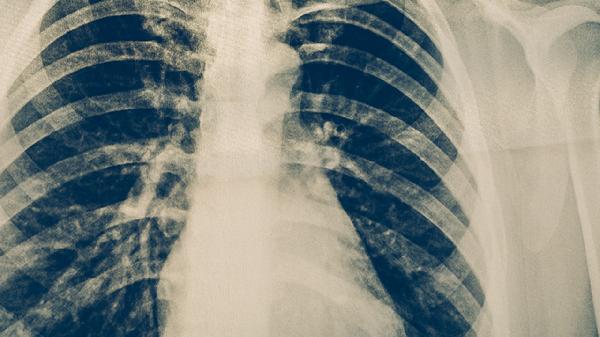

奈瑟卡他球菌肺炎是由奈瑟卡他球菌感染引起的肺部炎症,属于细菌性肺炎的一种。奈瑟卡他球菌肺炎可通过血常规检查、痰培养、胸部X线等方式诊断,治疗方式主要有阿莫西林克拉维酸钾片、头孢呋辛酯片、左氧氟沙星片、阿奇霉素分散片、盐酸莫西沙星片等药物。奈瑟卡他球菌肺炎可能与免疫力低下、慢性呼吸道疾病、长期吸烟、环境刺激、细菌耐药性等因素有关,通常表现为咳嗽、咳痰、发热、胸痛、呼吸困难等症状。

烟草中的有害物质会破坏呼吸道纤毛运动功能,导致细菌清除能力下降。吸烟者出现持续咳嗽伴黄脓痰时需警惕肺炎,应立即戒烟并进行胸部影像学检查。戒烟期间可配合尼古丁贴片、盐酸安非他酮缓释片等辅助治疗,同时加强肺部锻炼。